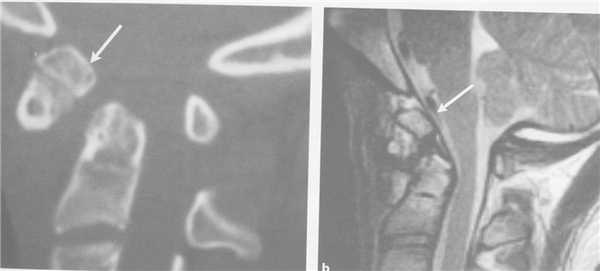

КТ. Перелом тела С2 (красные стрелки).

Особую категорию составляют пациенты, у которых, несмотря на наличие неврологической симптоматики, не выявляется изменений при рентгенографии или КТ. Число таких пациентов составляет около 10%. Среди различных механизмов подобных травм наиболее вероятна кратковременная компрессия спинного мозга задней продольной связкой и дисками, либо, жёлтой связкой и пластиной дуги. Посколько резкие сгибания и разгибания наблюдаются при высокой подвижности в сегментах, такие травмы более вероятны в шейном отделе позвоночника. Спондилолиз усугубляет эту ситуацию, приводя к центральному синдрому спинного мозга. В этих случаях необходимой является МРТ позвоночника. Характерными находками, которые мы часто видим при травмах при МРТ в СПб, являются отёк спинного мозга и гематома, причём последняя при МРТ позвоночника плохим прогностическим фактором в отношении восстановления неврологического дефицита. К наиболее тяжелым осложнениям шейной травмы относится расслоение магистральных артерий, определяемое по МРТ, МРА или КТ и КТА. В высоком поле такой вид травм лучше виден чем в открытом МРТ. МРТ СПб позволяет выбирать место МРТ, однако, острая травма шейного отдела позвоночника требует высокоспециализированного нейрохирургического отделения

МРТ шейного отдела позвоночника. Острая травма. Компрессия спинного мозга, отек и контузия. Сагиттальная Т2-взвешенная МРТ.